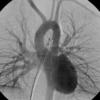

PA angio

Fig 4